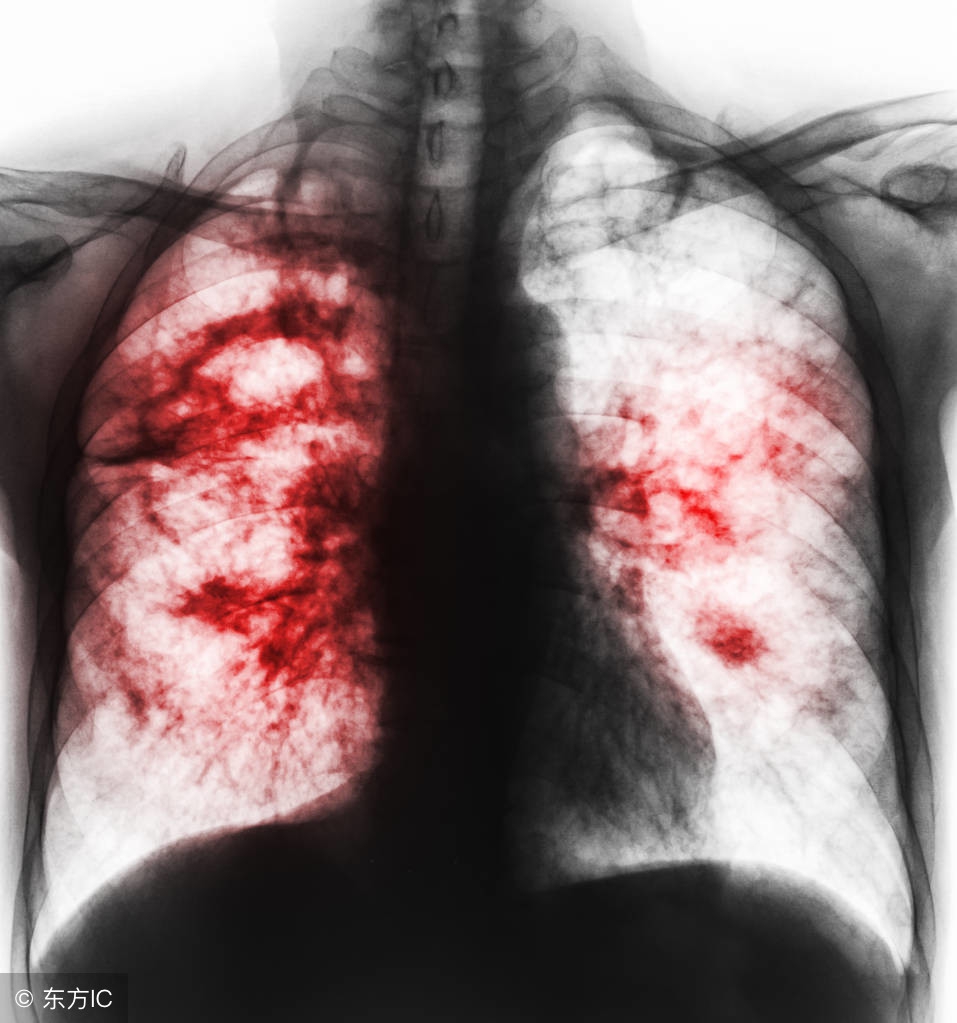

很多肺癌患者,由于没有早期发现病症,耽误了最佳治疗时间,发展成为肺癌中晚期,尽管治疗效果没有早期好,但肺癌中晚期治疗方案也会根据患者自身的情况进行改进,中医对于中晚期肺癌治疗有一定的研究。肺癌中晚期治疗方案主要是抑制病情再度恶化,减缓患者病痛折磨,提升患者的生活品质为主要原则,这一点上,中医食疗偏方很有发言权。

肺癌中晚期治疗方案